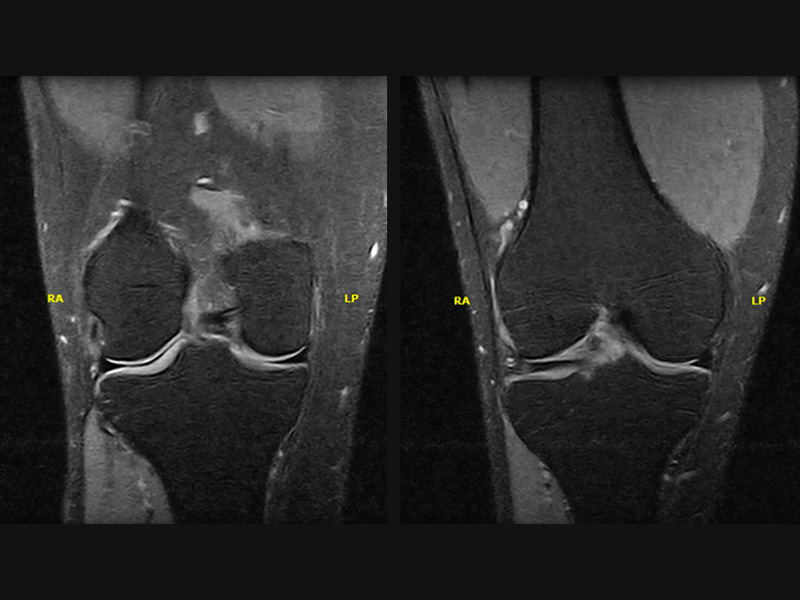

Klinické snímky